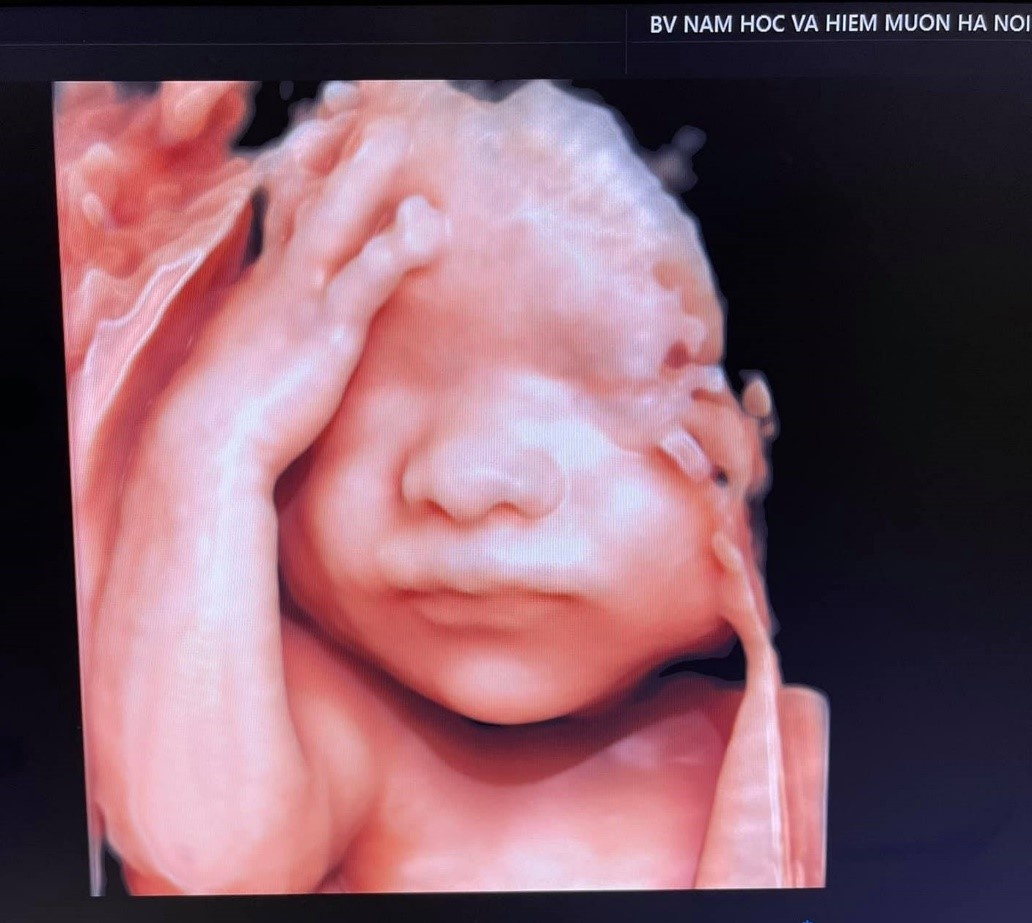

Hình ảnh thai nhi qua siêu âm 5D.

“Ngoài cung cấp hình ảnh em bé theo thời gian thực để bố và mẹ quan sát được các cử chỉ của con, hệ thống siêu âm 5D còn hiệu quả trong chẩn đoán các bất thường thai sớm ở tim, mạch, thần kinh, hệ xương... Kỹ thuật này có khả năng quan sát xuyên thấu với các tính năng chuyên dụng, hoặc tái tạo các mặt cắt khó khi tư thế em bé khó khăn cho việc khảo sát. Đây là những tính năng mà hệ thống siêu âm 3D hay 4D không đủ sức làm được” - bác sĩ Khanh cho biết.